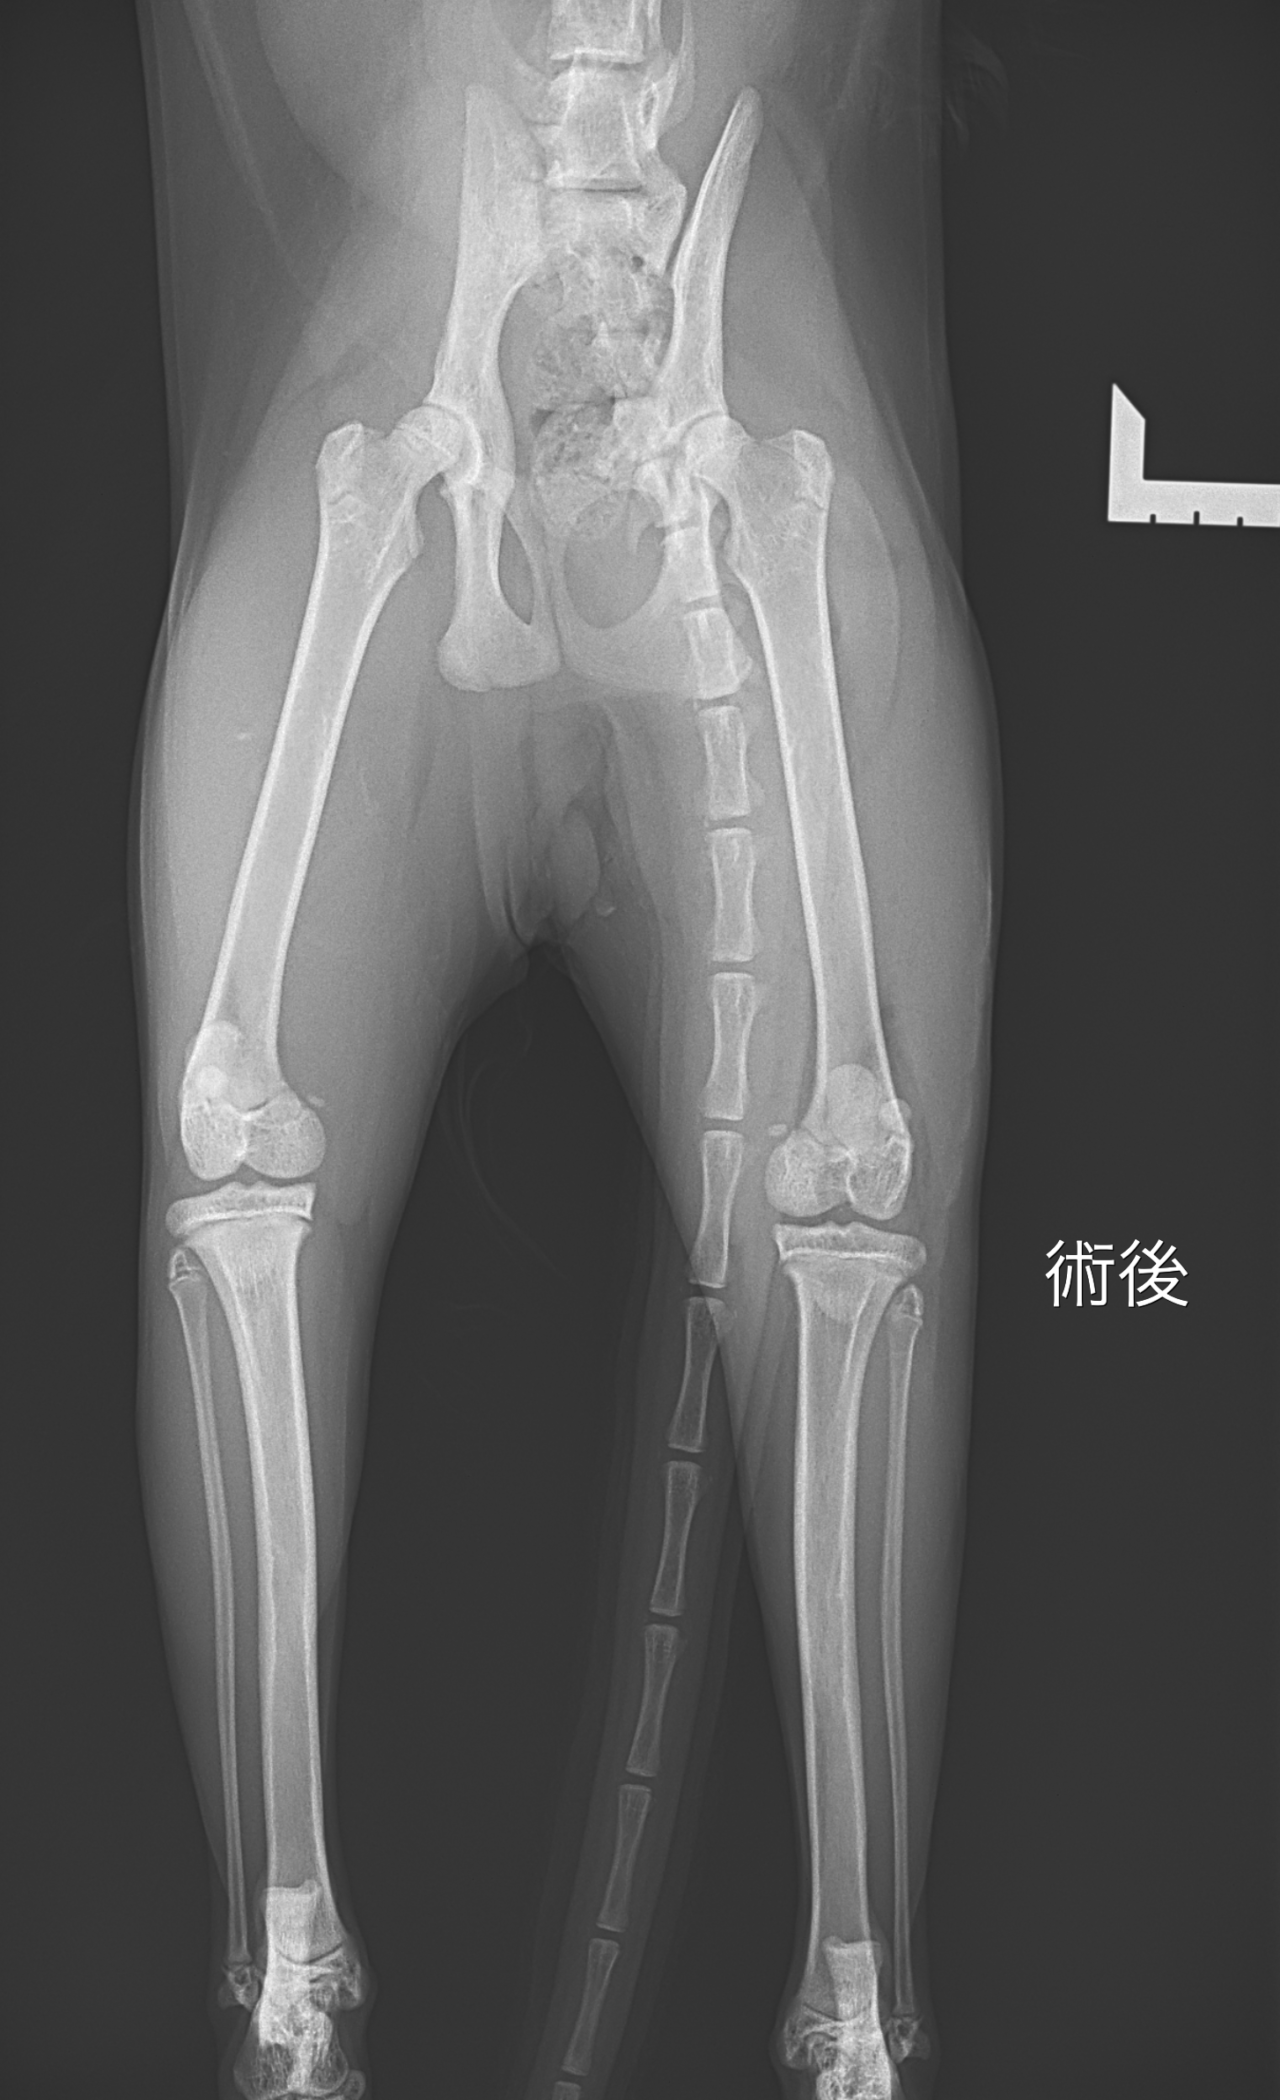

猫の膝蓋骨内方脱臼(Medial Patellar Luxation:MPL)Grade 4

猫 膝蓋骨内方脱臼(Medial Patellar Luxation:MPL)Grade 4に対して、大腿骨滑車造溝、膝蓋骨形成術、内側広筋切断(内側支持組織リリース)を実施した。膝関節外側より関節包を切開し、膝関節を展開した、膝蓋骨は常時内方に脱臼しており、用手整復は不可能であった。内側広筋および内側支持組織の著明な緊張を認めた。大腿骨滑車溝は浅く、滑車溝の形成不全が確認された。まず、大腿骨滑車造溝術を実施した。滑車軟骨を温存するよう留意しながら、大腿骨滑車溝にブロック状の形成術を行い、適切な深さおよび形状となるよう滑車溝を形成した。さらに、膝蓋骨形成術を行い、膝蓋骨の両辺縁を整え、滑車溝との適合性を向上させた。続いて内側広筋切断(内側支持組織リリース)を実施した。内側広筋の過度な牽引力を解除する目的で、内側支持組織を慎重に切離し、膝蓋骨の可動性が改善することを確認した。術後、膝関節の屈伸を行い、全可動域において膝蓋骨が滑車溝内を安定して走行し、脱臼傾向がないことを確認した。十分に洗浄後、関節包、皮下組織、皮膚を定法に従い縫合した。